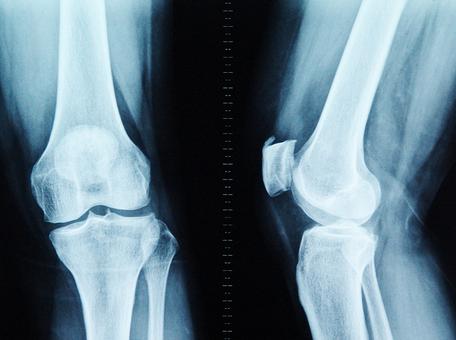

在人体的“骨骼大厦”中,胶原蛋白是钢筋,钙、镁、磷等骨质就是水泥。30岁后,胶原蛋白流失加剧,胶原框架老化变细、变脆甚至断裂,出现缺口;钙、镁、磷等骨质无法正常沉积在骨骼上,从缺口中游离出来;随着肢体的活动和负重,游离的骨质慢慢堆积在活动频繁、承重量大的关键部位(如颈椎、腰椎、膝关节、足跟),骨刺由此产生。